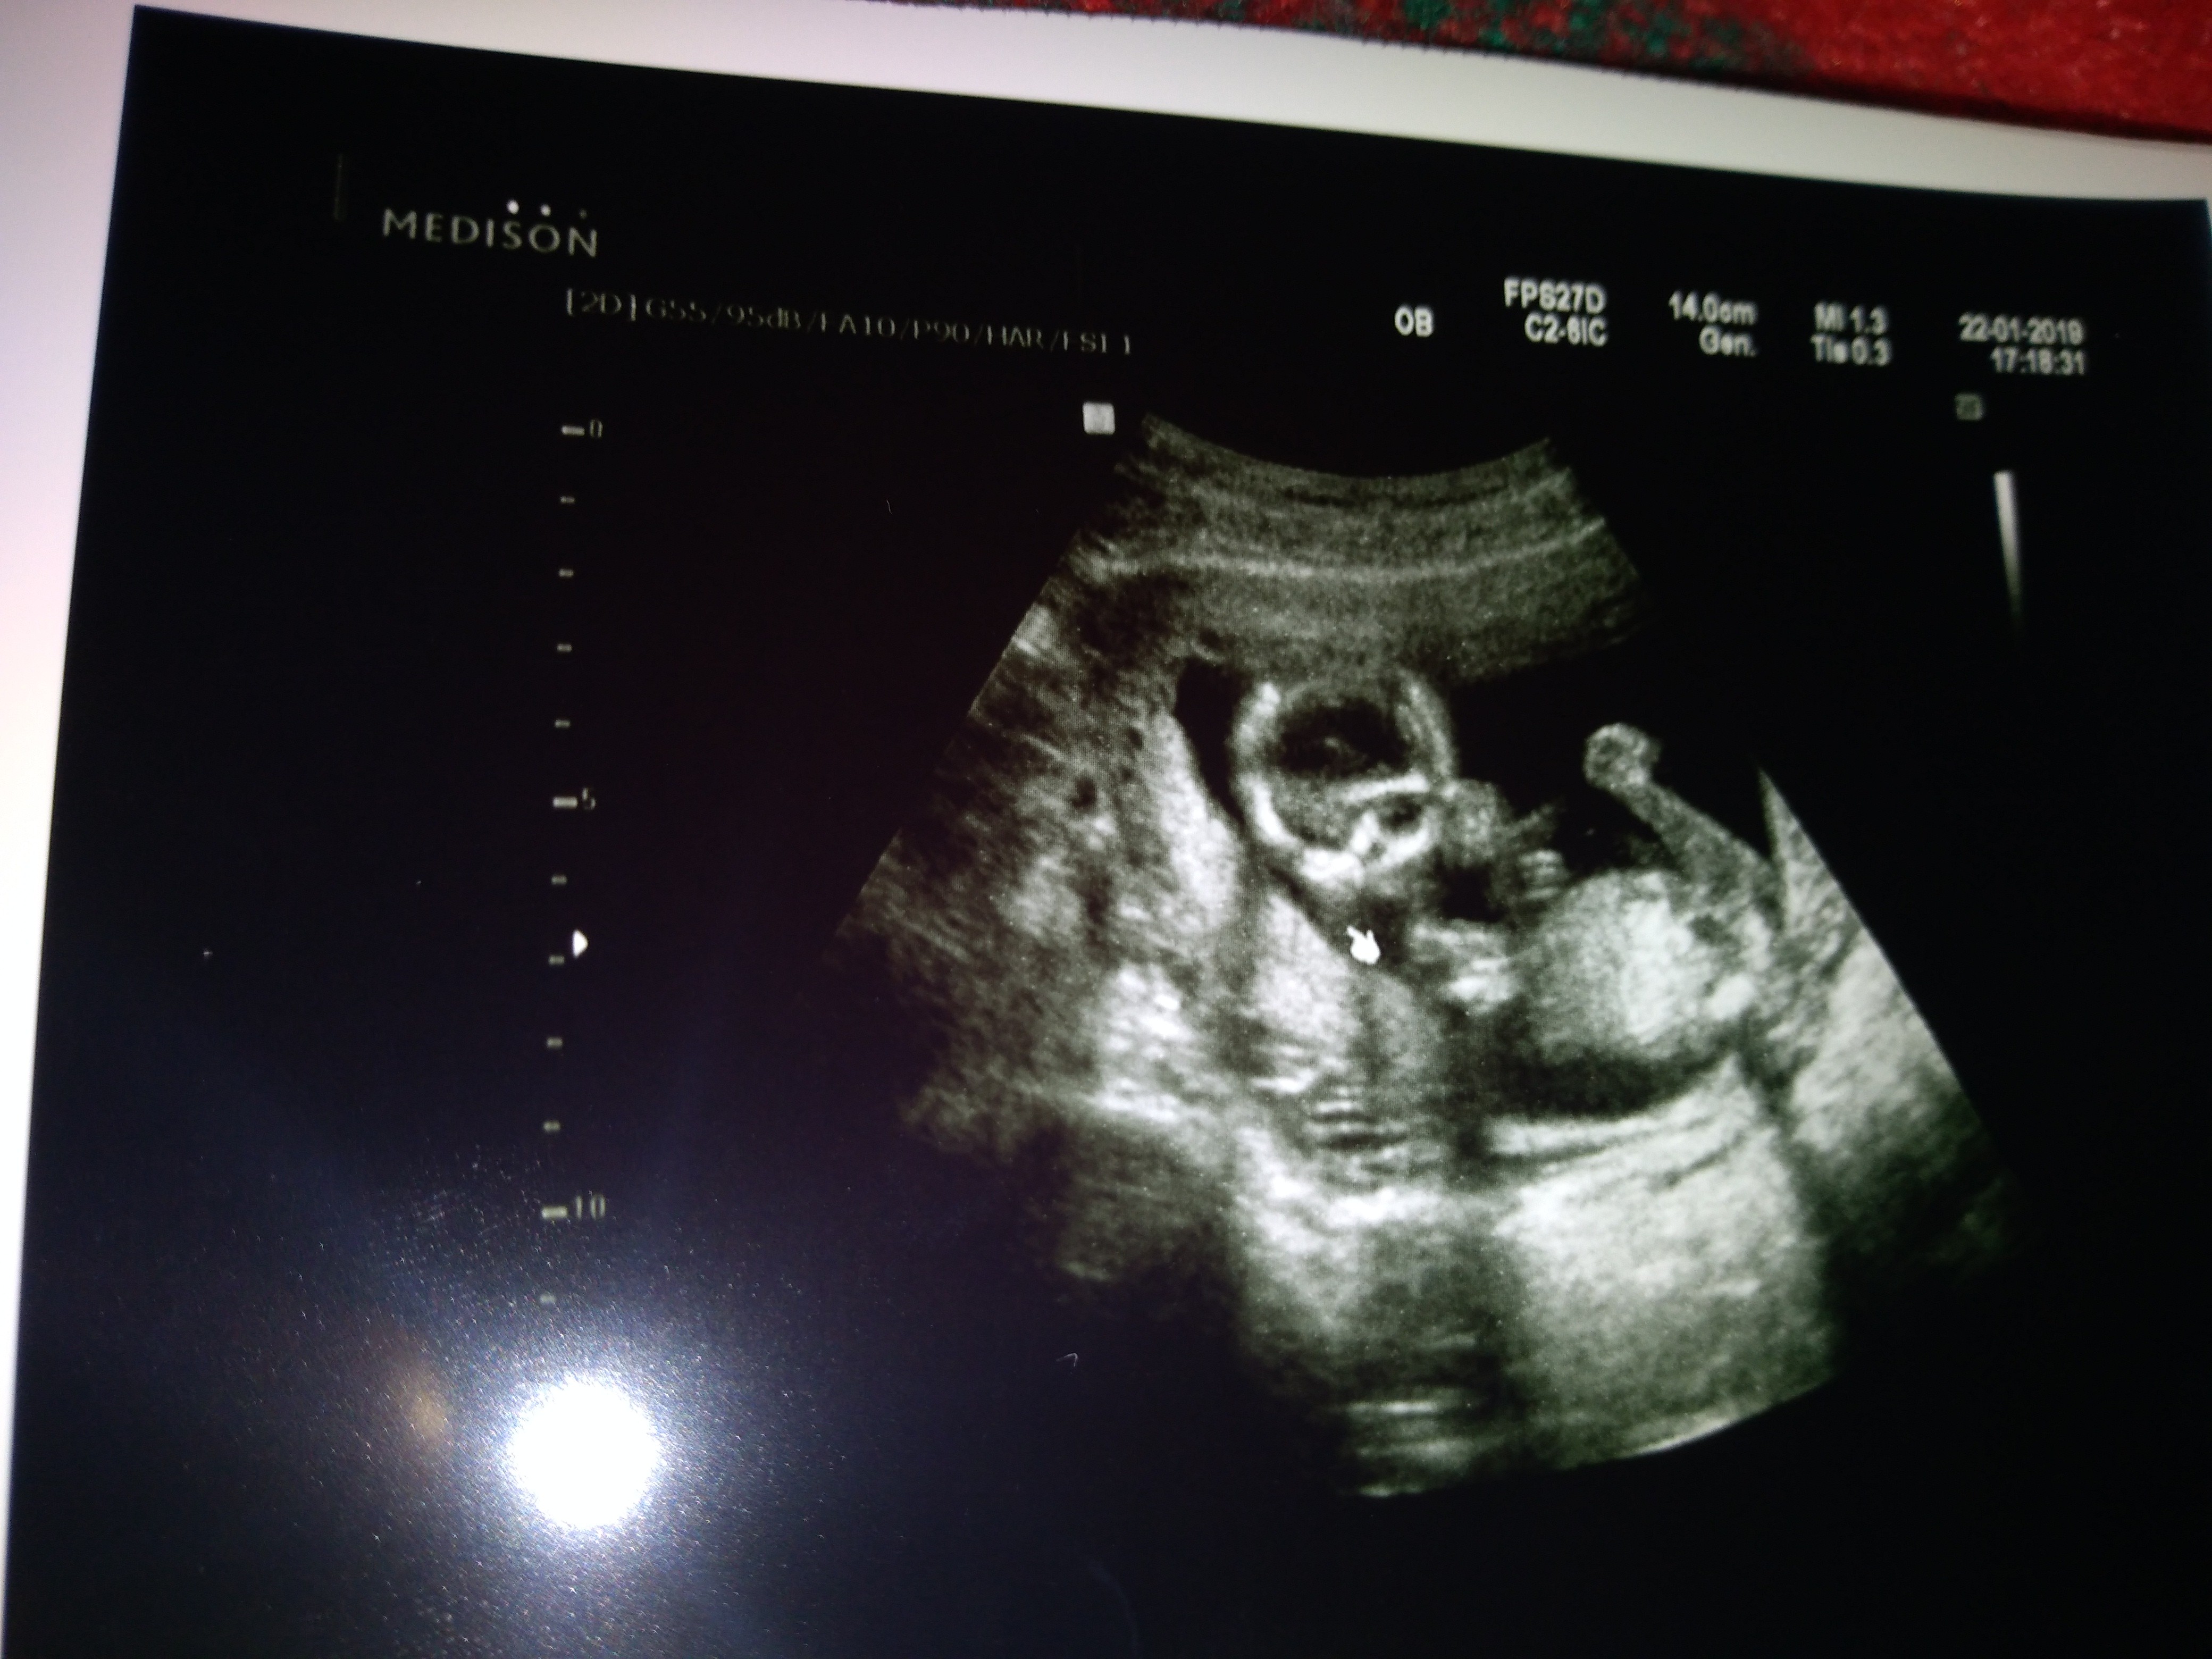

Hej rzadko piszę ale często was czytam ja właśnie po wizycie (16+2) bąbelek ma 13 cm i waży 15 dkg, prawdopodobnie dziewczynka, mąż wariuje z radości

Załączniki

• IMG_20190122_182626.jpg

IMG_20190122_182626.jpg

1,6 MB · Wyświetleń: 129